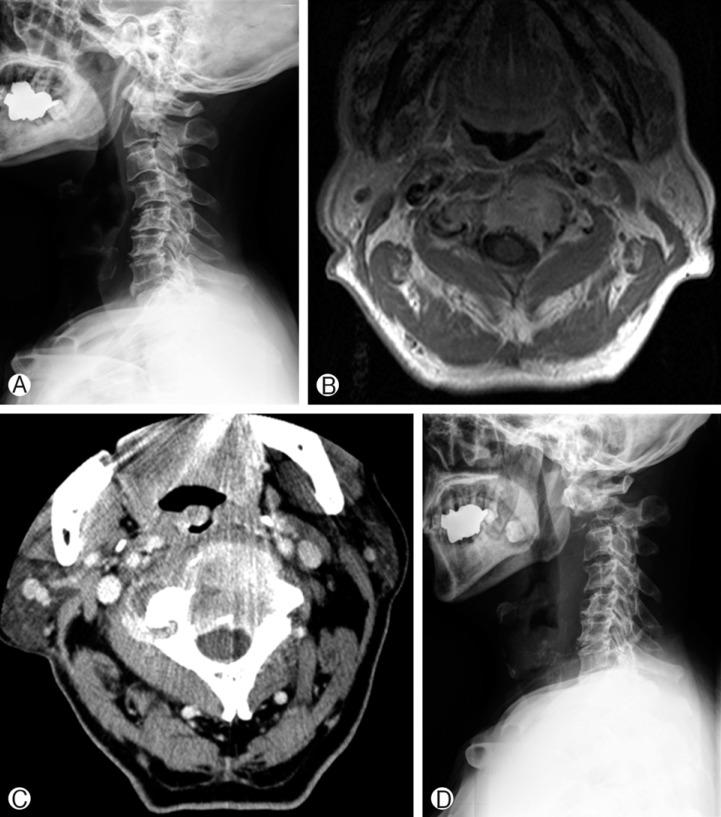

This study consisted of 72 patients who underwent SRS due to spinal tumors. In them, whether post-SRS VCF developed or not was investigated. We retrospectively analyzed their medical records and radiological imaging data. VCF was diagnosed with X-ray and magnetic resonance imaging (MRI). The incidence, time to development and risk factors for VCF were investigated. Age, sex, whole vertebral body involvement rate, vertebral body osteolysis rate, pre-SRS spinal deformity, spinal instability neoplastic score (SINS), spinal canal encroachment, lesion level, and radiation dose were analyzed as potential risk factors. A multi-variate logistic regression model was used for statistical analysis.

In our study population, VCF was observed in 26 patients (36%). The mean time to VCF development was 1.5 months. Using uni-variate analyses, the significant risk factors were pre-SRS spinal deformity, SINS, vertebral body osteolysis rate, and whole vertebral body involvement rate. However, using multi-variate analyses, the only significant risk factor was vertebral body osteolysis rate. The patients whose vertebral body was destroyed by more than 60% showed an 8.4 times higher risk of VCF than those who had vertebral body destruction of less than 60%(p=0.016).

The most significant prognostic factor for post-SRS VCF was vertebral body osteolysis rate, rather than whole vertebral body involvement rate. When more than 60% of the vertebral body was destroyed, the risk of VCF or spinal deformity was high.